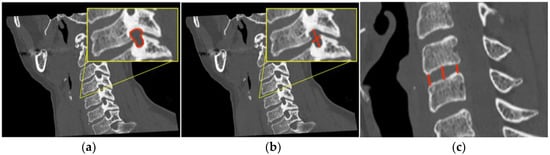

Figure 2.

In (a) the outline of the foramen is drawn in yellow and in (b) the measurement of the intervertebral foramen antero-posterior (A-P) and cranio-caudal (C-C) diameters are drawn in red, which means foramen width and height, respectively, are shown with red lines. In (c) the red lines show the antero, centrum and postero disc height measurement.

Through the use of MIP and MPR cervical bone-window CT scans, the correct site for measurements at each cervical segment (surgical or above or below) was selected matching the midline point on the anterior surface of the vertebral body on coronal view with the intervertebral foramen plane on axial view, and then adjusted with a plane parallel to the inferior endplate of the level above on the sagittal view. (Figure 1). The antero-posterior (A-P) and cranio-caudal (C-C) diameters of each foramen (surgical and adjacent levels, right and left) were manually measured (Figure 2a). The measurement of the C-C diameter was considered similar to the height of the foramen, and in sagittal reconstruction it was the distance between the midpoint of the upper and lower corresponding pedicles; the measurement of the A-P diameter was considered similar to the width of the foramen, and in sagittal reconstruction it was the distance between the anterior and the posterior border of the inferior intervertebral notch. For the intervertebral disc measurement, the disc height was measured in the anterior, middle, and posterior third on sagittal CT scans. The measure of the intervertebral disc space was considered from the corresponding point (anterior, middle, and posterior) of the inferior endplate of the upper vertebral body to the superior endplate of the lower vertebral body (Figure 2b). CT scans were performed before and within 72 h after surgery, usually the day after the procedure.